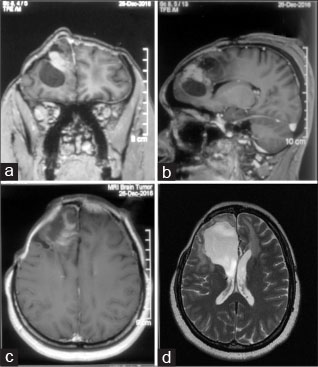

A 37-year-old female with anaplastic astrocytoma in the right frontal lobe underwent supratentorial craniectomy for a recurrent right frontal tumor in the neurosurgery department and was discharged uneventfully [Figure 1a], [b], [c], [d]. She had a history of undergoing surgery and radiotherapy for the same disease. She was planned for reradiation and rechallenge with temozolomide; however, after about a month (post-2nd surgery), she complained of fever, headache, vomiting, and neck rigidity. Her Glasgow Coma Scale = 15/15 and Karnofsky Performance Status = 70. She had a cerebrospinal fluid (CSF) leak from the operative site and a fever of 39.4°C. Laboratory investigations from peripheral blood indicated increased white blood cell (WBC) count of 14.91 × 109/L (4.0–10.0); increased absolute neutrophil count of 10.74 × 109/L (2.0–7.0) at 88.6% (40.0–80.0); decreased lymphocyte count of 0.87 × 109/L (1.0–3.0) at 5.9% (20.0–40.0); increased CSF protein = 449 mg/dL (normal: 15–45 mg/dl); lactic dehydrogenase = 250 U/L (normal: 100–190 U/L); C-reactive protein = 10.8 mg/dl (reference range: 0–0.33); and decreased CSF sugar level = 36 mg/dl (corresponding random blood sugar = 78 mg/dL). She had received day 1 of salvage temozolomide before the symptoms appeared, following which it was discontinued. Her lumbar CSF sample was sent to the microbiology laboratory for bacterial culture and drug sensitivity, blood sample for routine viral markers, malaria antigen testing, and the patient was empirically started with injection vancomycin (500 mg 6 hourly) and cefoperazone–sulbactam (2 g 12 hourly). The tests for malaria antigen detection by immune chromatographic assay were negative; dengue-NS1 antigen, IgM, and IgG antibodies were not detected. The viral markers for hepatitis B surface antigen, human immunodeficiency virus, and anti-hepatitis C virus antibodies were also nonreactive. Gram staining of CSF showed polymorphonuclear cells and Gram-negative bacilli. On culturing the CSF on blood agar and nutrient agar for 24 h, yellow-pigmented colonies with fruity odor were obtained [Figure 2a] and [b]. MacConkey agar did not show any growth. Gram staining of the colonies on blood agar suggested a pure culture of Gram-negative bacilli. Identification of the isolate was also performed on the VITEK-2 (BioMérieux, Marcy-l'Etoile, France) automated identification system, which reported Myroides spp. and its AST MIC pattern. M. odoratus was presumptively identified by performing the desferrioxamine (250 μg-disc) susceptibility testing; M. odoratus being desferrioxamine susceptible while the other species M. odoratimimus being nonsusceptible.[5] The minimum inhibitory concentrations (MICs) (μg/ml) were found to be ≥64, ≥16, ≥4, ≤4, 8, ≤8, ≤0.25, ≤0.25 μg/ml for amikacin, gentamicin, ciprofloxacin, piperacillin/tazobactam, ceftazidime, cefoperazone-sulbactam, imipenem, and meropenem, respectively. However, susceptibility interpretation is not possible due to lack of standard Clinical and Laboratory Standards Institute (CLSI) or EUCAST interpretive breakpoints for Myroides spp. These MICs and interpretation were provided by the VITEK-2 using GN AST-N 281-NLF cards. The VITEK-2 identification and susceptibility testing system has been used for non-glucose-fermenting Gram-negative bacilli (including Myroides), and the results have been found to be acceptable in a study conducted by Hsieh et al. in 2009, which reported a 100% (n = 7) concordance of GN AST-N 281-NLF cards for reporting Myroides spp. with that of conventional identification methods.[6]

| Figure 1 Contrast-enhanced coronal, sagittal, and axial view of preoperative magnetic resonance imaging showing the tumor. (d) T2 axial image of the postoperative magnetic resonance imaging showing tumor excision